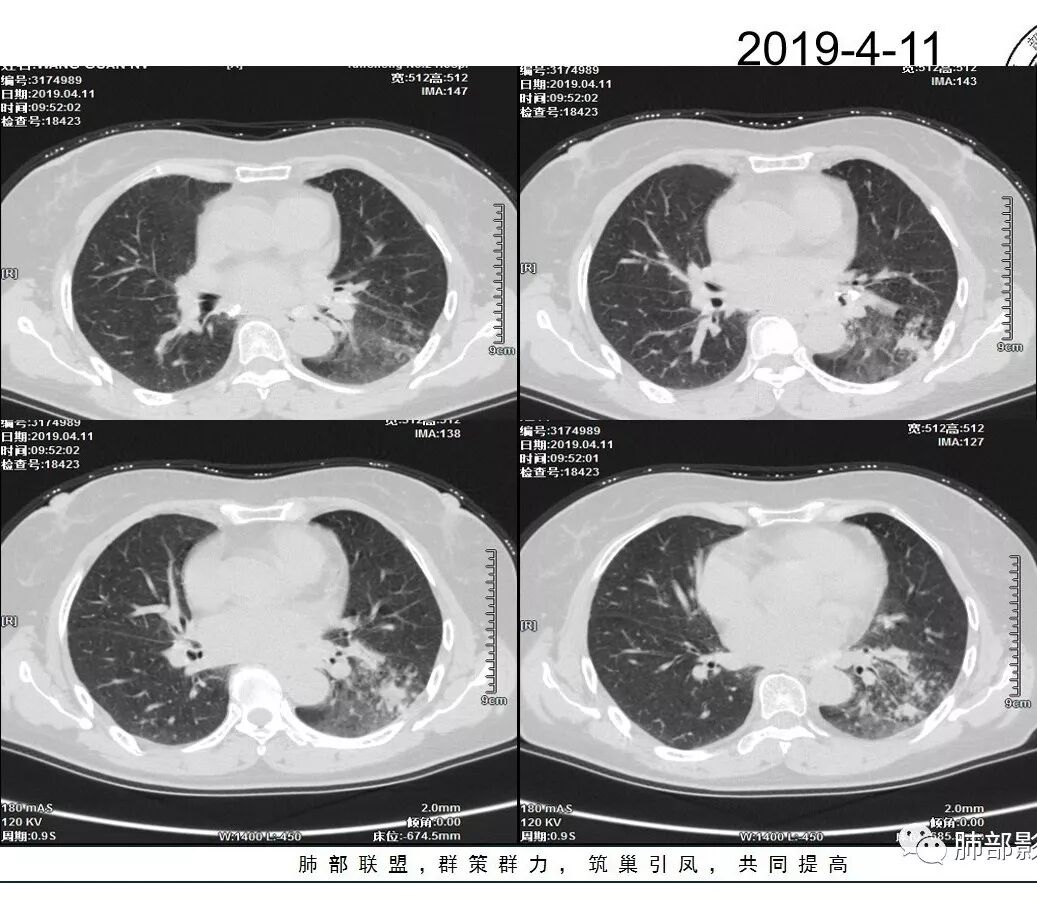

女性,57岁或67岁,咳嗽气短2月,伴发热2天。肿标及血常规(一)。左下肺实变+GGO,实变区增强强化,镜下见左下支气管狭窄,最后一次CT(4.11)较第一次CT(3.24)病灶有吸收。个别图像看不清(Tspot)。考虑:一元:肺炎型肺癌丶肺结核丶普通炎症?二元:结核合并癌?

2.左肺下叶片状影及多数有边界的结节影,较散,多形性,密度不均(注意许多老师提到这个特点还是比较明显的)。左肺下叶体积未见缩小。

3.病灶强化比较明显。

4.左下叶支气管壁增厚,管腔不均匀狭窄,没有堵塞

5.肺门纵隔见增大钙化淋巴结。提示曾经存在慢性病损可能。